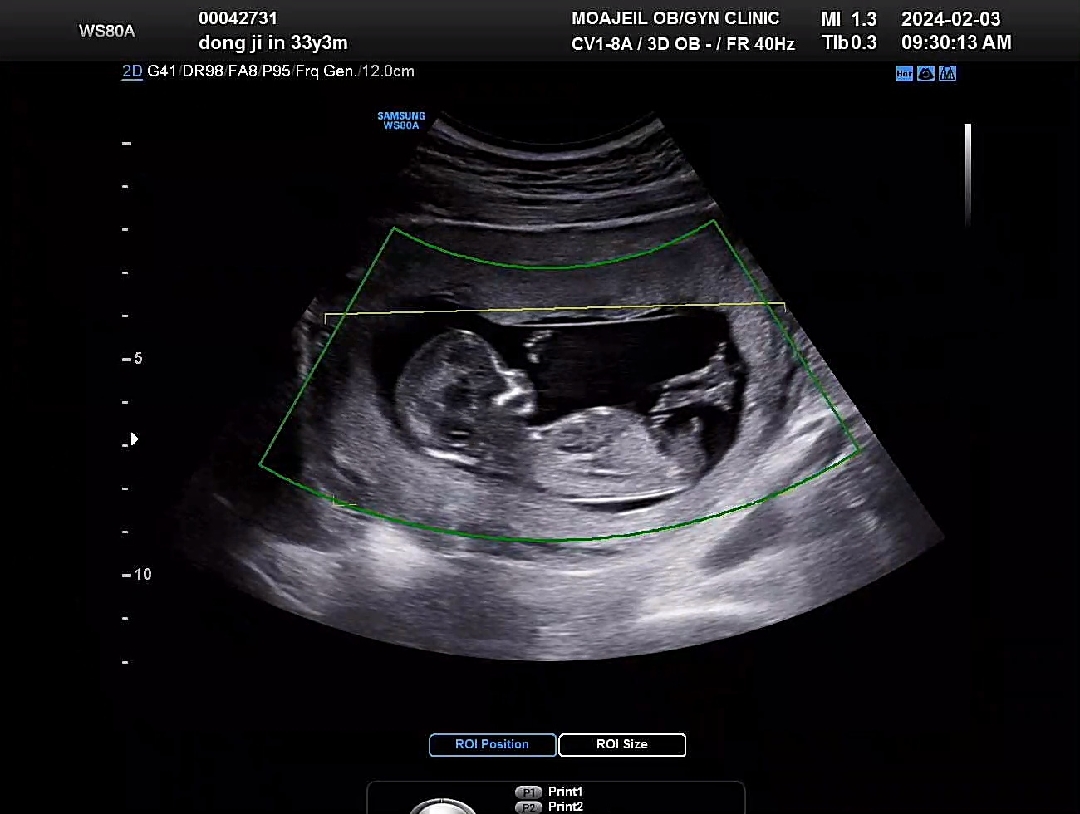

13주 각도법 봐주실 수 있나요???

13주 됐습니다 ㅎㅎ 성별이 궁금한데 각도법 볼 줄 아는분 계실까요??

아들같아요